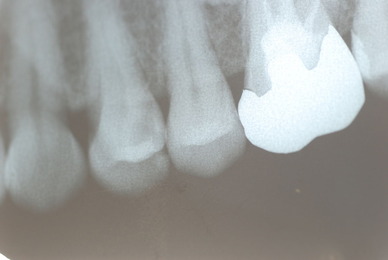

歯周病の疑いで東京のかなり遠方の方が来院されました。

驚くべきことですが、定期検診は受けていたそうです。しかしながら歯周病の指摘は受けたことがないそうです。

何故か?定期検診が虫歯のチェックのみになり、又肝心の歯周病の検査や歯周病の部分の予防や治療のためのブラシの使い方などを学んだ事がないのです。